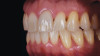

(17.) Case 2: Right- and left-side retracted profile views of the definitive all-ceramic restoration on the maxillary left central incisor.

Figure 17

Eight weeks after the initial start of the walking bleach procedure, the final layered lithium disilicate crown was tried-in and evaluated for function and esthetics. Upon patient approval, the intaglio surface of the crown was etched for 20 seconds with a 9.6% hydrofluoric acid etchant, rinsed, and then scrubbed with a 37.5% orthophosphoric acid solution to clean out any ceramic debris. The crown was then placed into an ultrasonic bath of 91% isopropyl alcohol for 5 minutes, after which the intaglio surface was coated with silane and placed under a warm air dryer for 1 minute. A translucent self-adhesive resin cement was used to bond the final restoration to the preparation. The patients both stated that they approved of the form, function, and esthetics of the definitive restoration and that they were very pleased with the final results (Figure 13 through Figure 18). Routine periodic evaluations and radiographs were scheduled to monitor their oral health and esthetics.